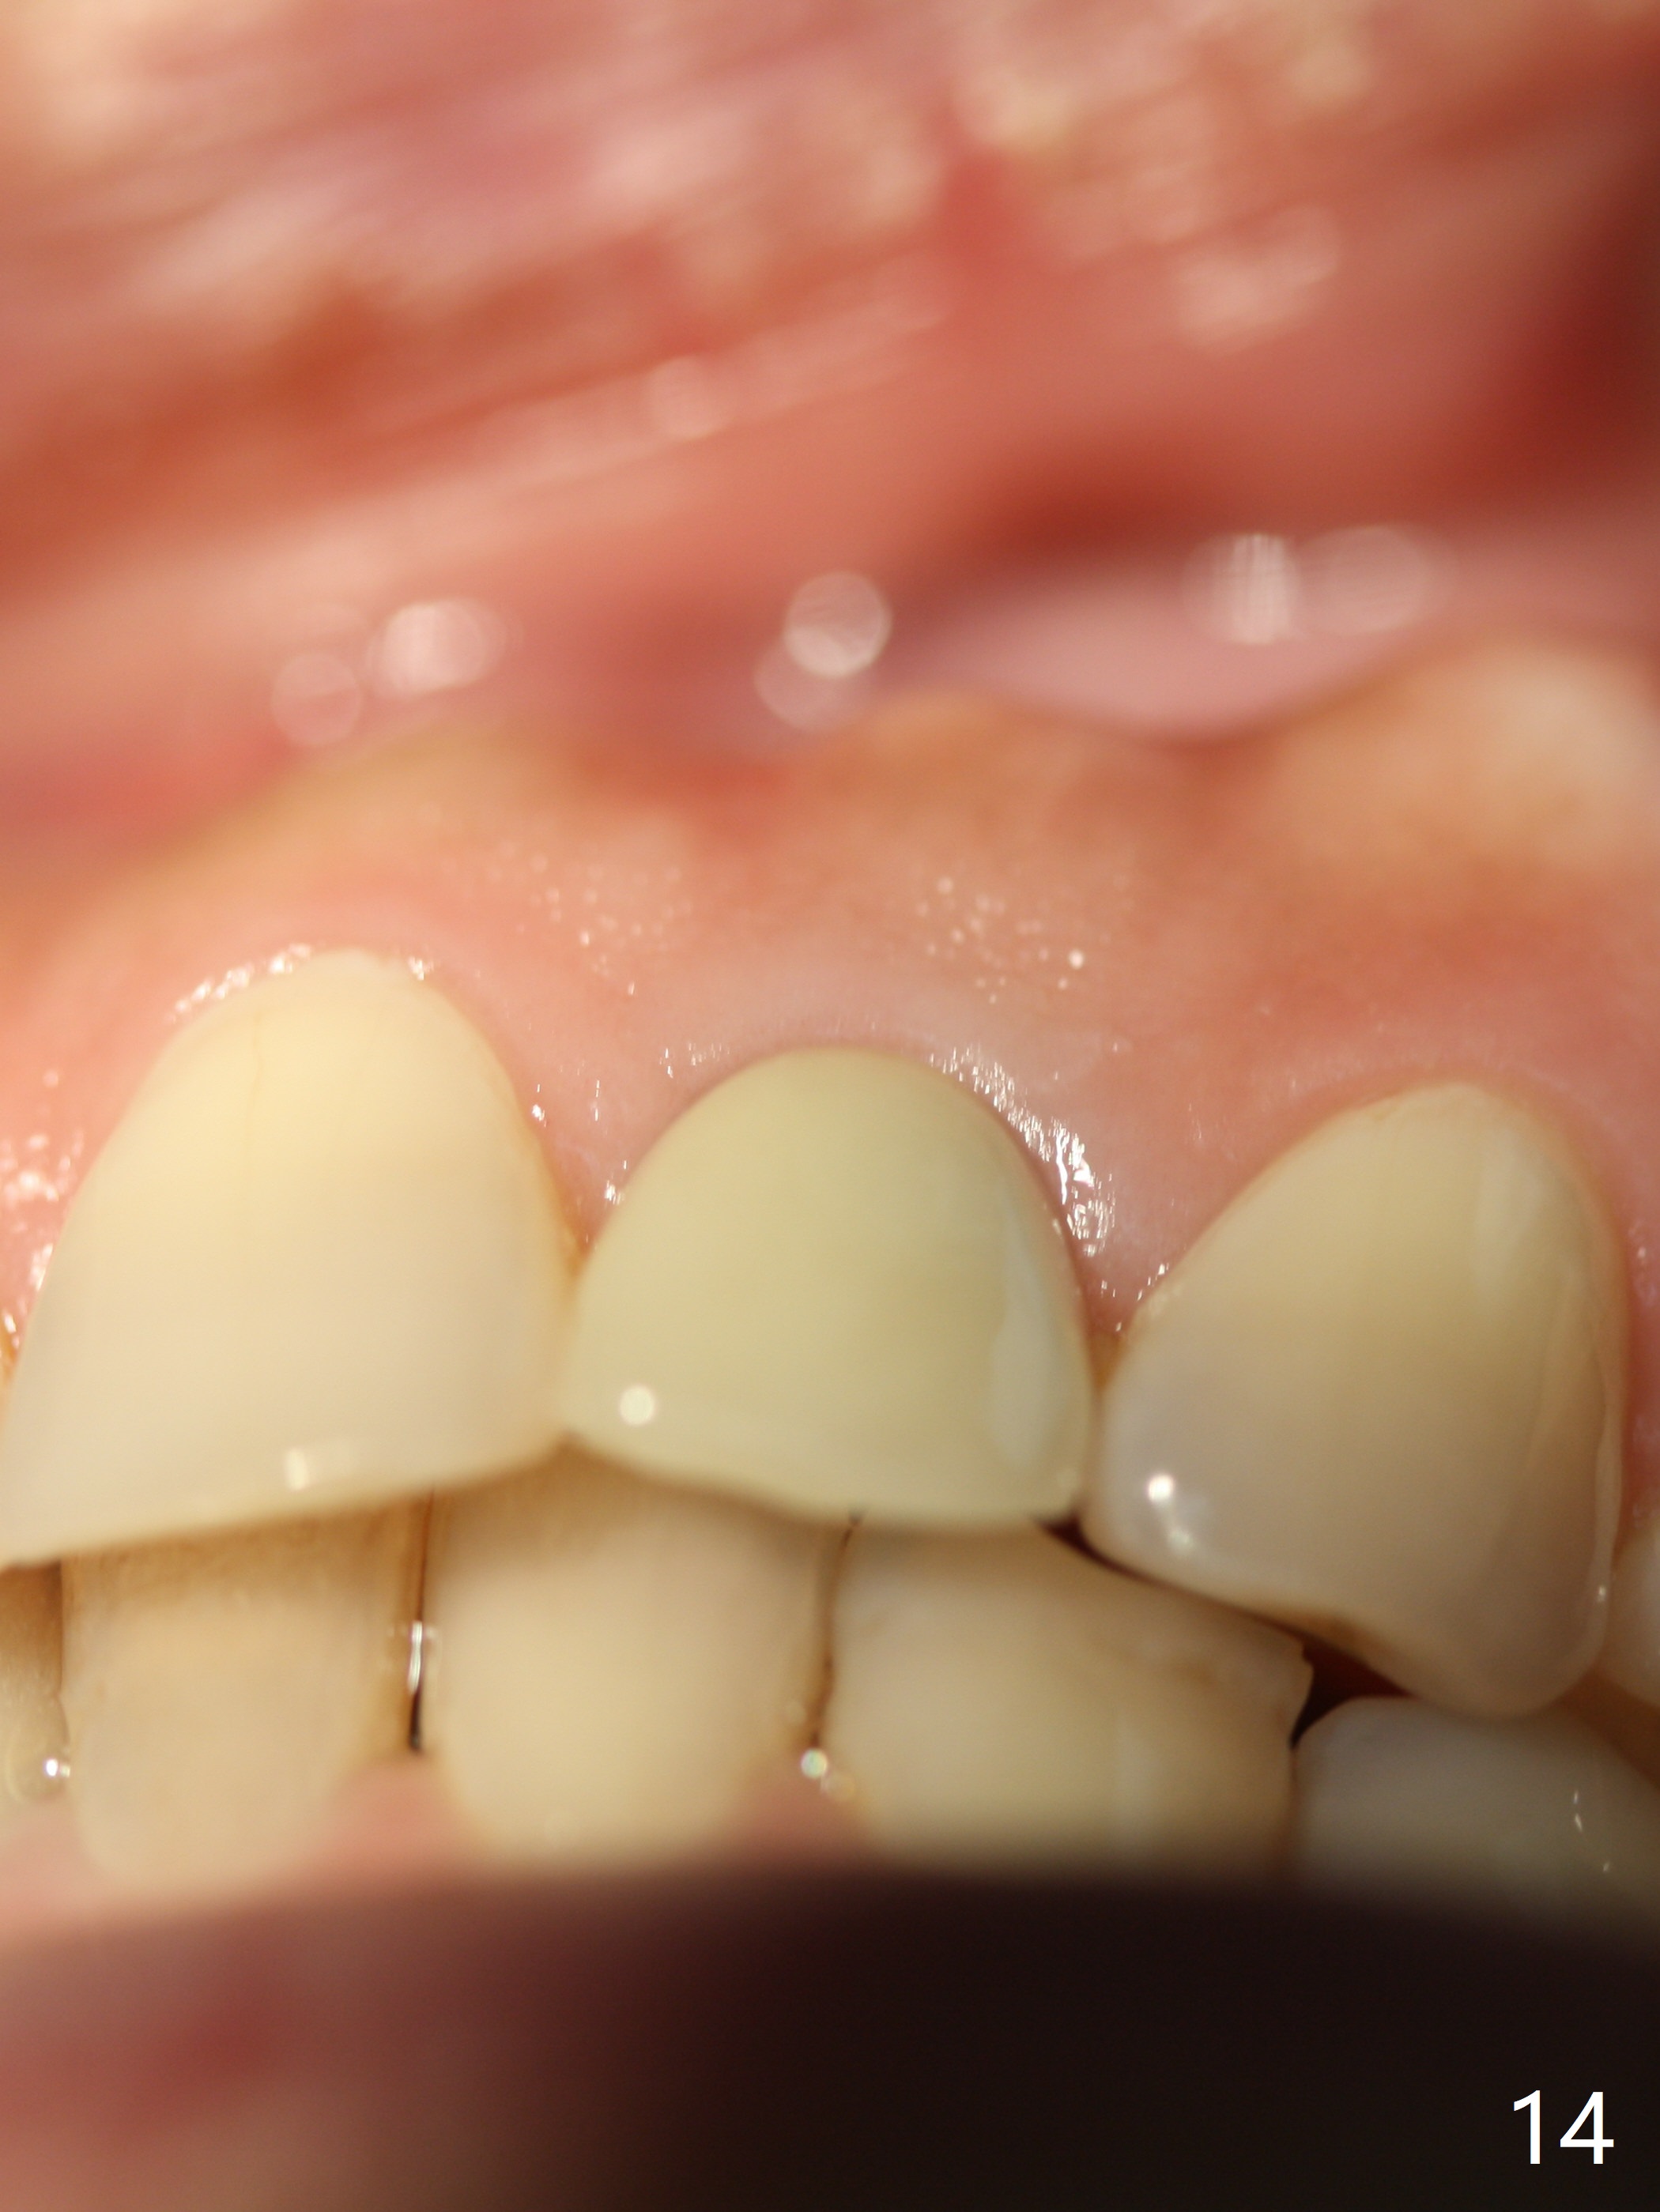

Dense bone forms immediately next to the implant 3 years 5 months post cementation (Fig.13) without gingival recession (Fig.14,15). In fact, the buccal plate maintains root contour over the implant (Fig.15 *). The root prominence remains 6 years 3 months post cementation (Fig.16-18 *). Appreciate the labial concavity associated with implant placement 6 years 9 months post cementation (Fig.19). The implant must have been placed quite palatal.